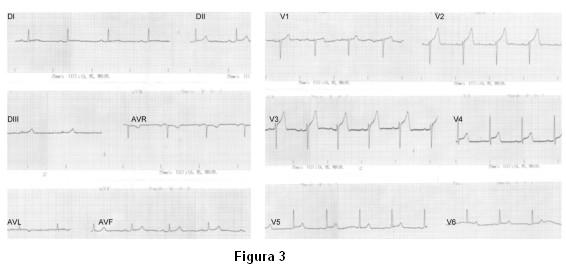

A las 72 horas reitera episodio de dolor torácico intenso de reposo. Nuevo ECG (figura 3): ritmo sinusal de 70 cpm, nuevo supradesnivel supracóncavo del segmento ST de V1 a V4 de hasta 4 mm con ondas T acuminadas en igual topografía. Se administra dinitrato de isosorbide 10 mg sublingual con alivio del dolor y descenso del segmento ST.